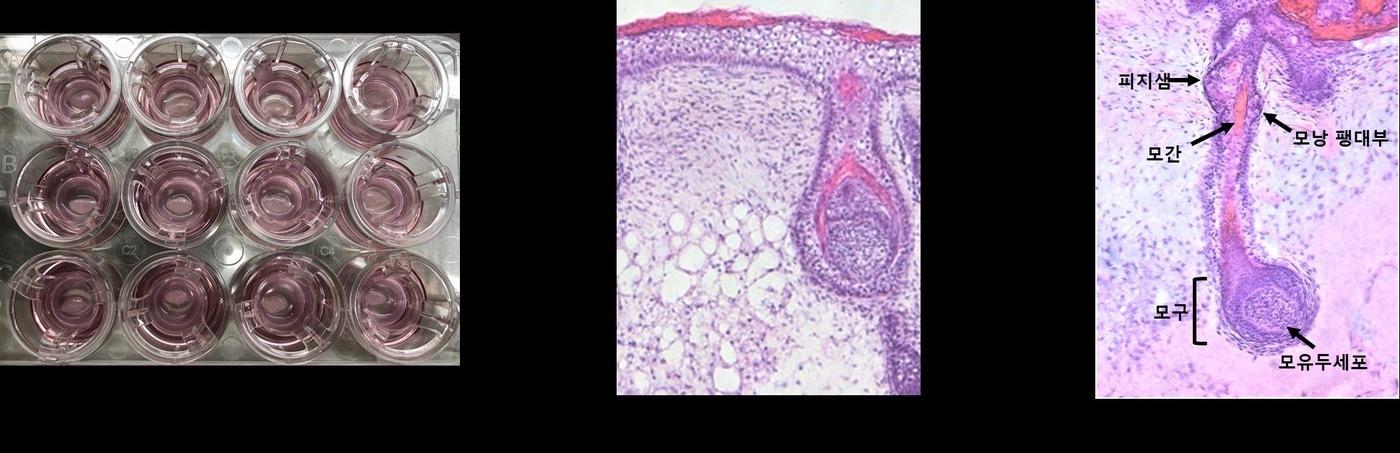

본문 이미지 - 강스템바이오텍의 피부 오가노이드는 실제 피부와 동일한 형태의 3차원 구조로써 표피층, 진피층, 피하지방 및 모낭조직까지 완벽히 구현됐다.(강스템바이오텍 제공)

강스템바이오텍의 피부 오가노이드는 실제 피부와 동일한 형태의 3차원 구조로써 표피층, 진피층, 피하지방 및 모낭조직까지 완벽히 구현됐다.(강스템바이오텍 제공)